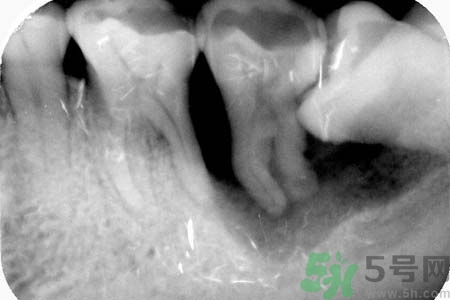

針對(duì)長(zhǎng)歪了的智齒,專家建議及早的拔智齒處理,至于拔智齒多少錢,一般來說拔智齒多少錢在150—300元左右,具體根據(jù)智齒的拔除難易程度而定,如果智齒阻生較為嚴(yán)重的話,在拔智齒前還需要拍x光片以了解智齒及鄰牙的具體結(jié)構(gòu),這種情況下,拔智齒多少錢相對(duì)要貴一些。

三級(jí)醫(yī)院阻生智齒拔除術(shù)收費(fèi)標(biāo)準(zhǔn)是85元,加上切開縫合放藥等也不到200元。拍牙片不計(jì)入(牙片有10元的也有80元的)這顆牙較難拔,術(shù)后反應(yīng)也大,最好去正規(guī)醫(yī)院拔。